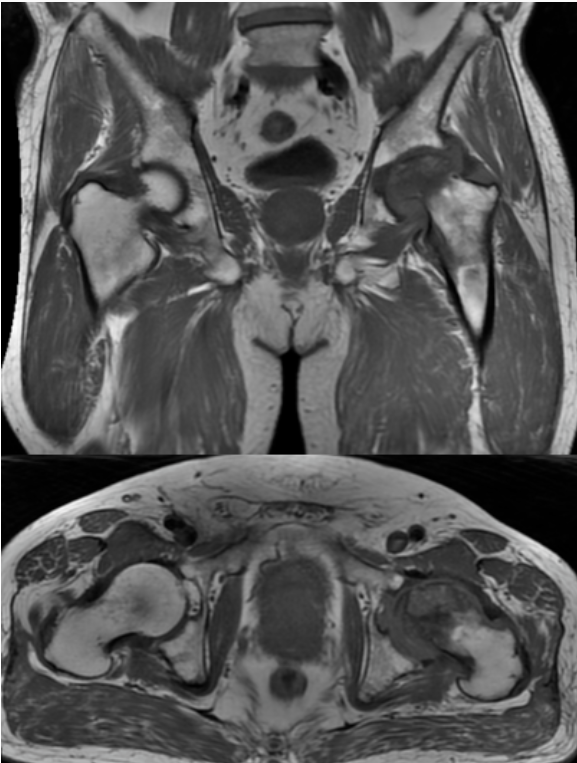

MRI结果显示,王先生的左侧股骨头已经变扁,出现局部塌陷。

左侧股骨头变扁,局部塌陷,骨质内见线状T1WI低信号,髋臼及股骨近端骨松质见片状T1WI低、T2WI压脂高信号,DWI高信号,周围滑膜增厚,邻近软组织肿胀,PD压脂信号增高,关节腔少量积液。

多序列、多参数成像:如同本例中运用的T1WI、T2WI压脂、DWI、PD压脂等不同序列,能从血流、水分、细胞密度等多个维度评估病变性质,为医生提供全面的诊断信息。